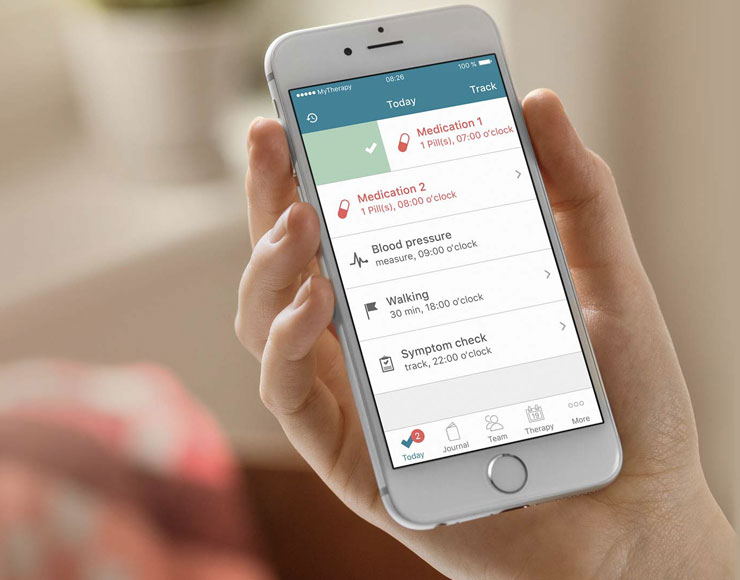

MyTherapy, l’app medica che può salvare la vita

Un'app per sostenere i pazienti dove le terapie spesso falliscono: MyTherapy incoraggia i pazienti a condividere i progressi con il proprio medico e ottenere informazioni sui miglioramenti e sulla coerenza dei trattamenti